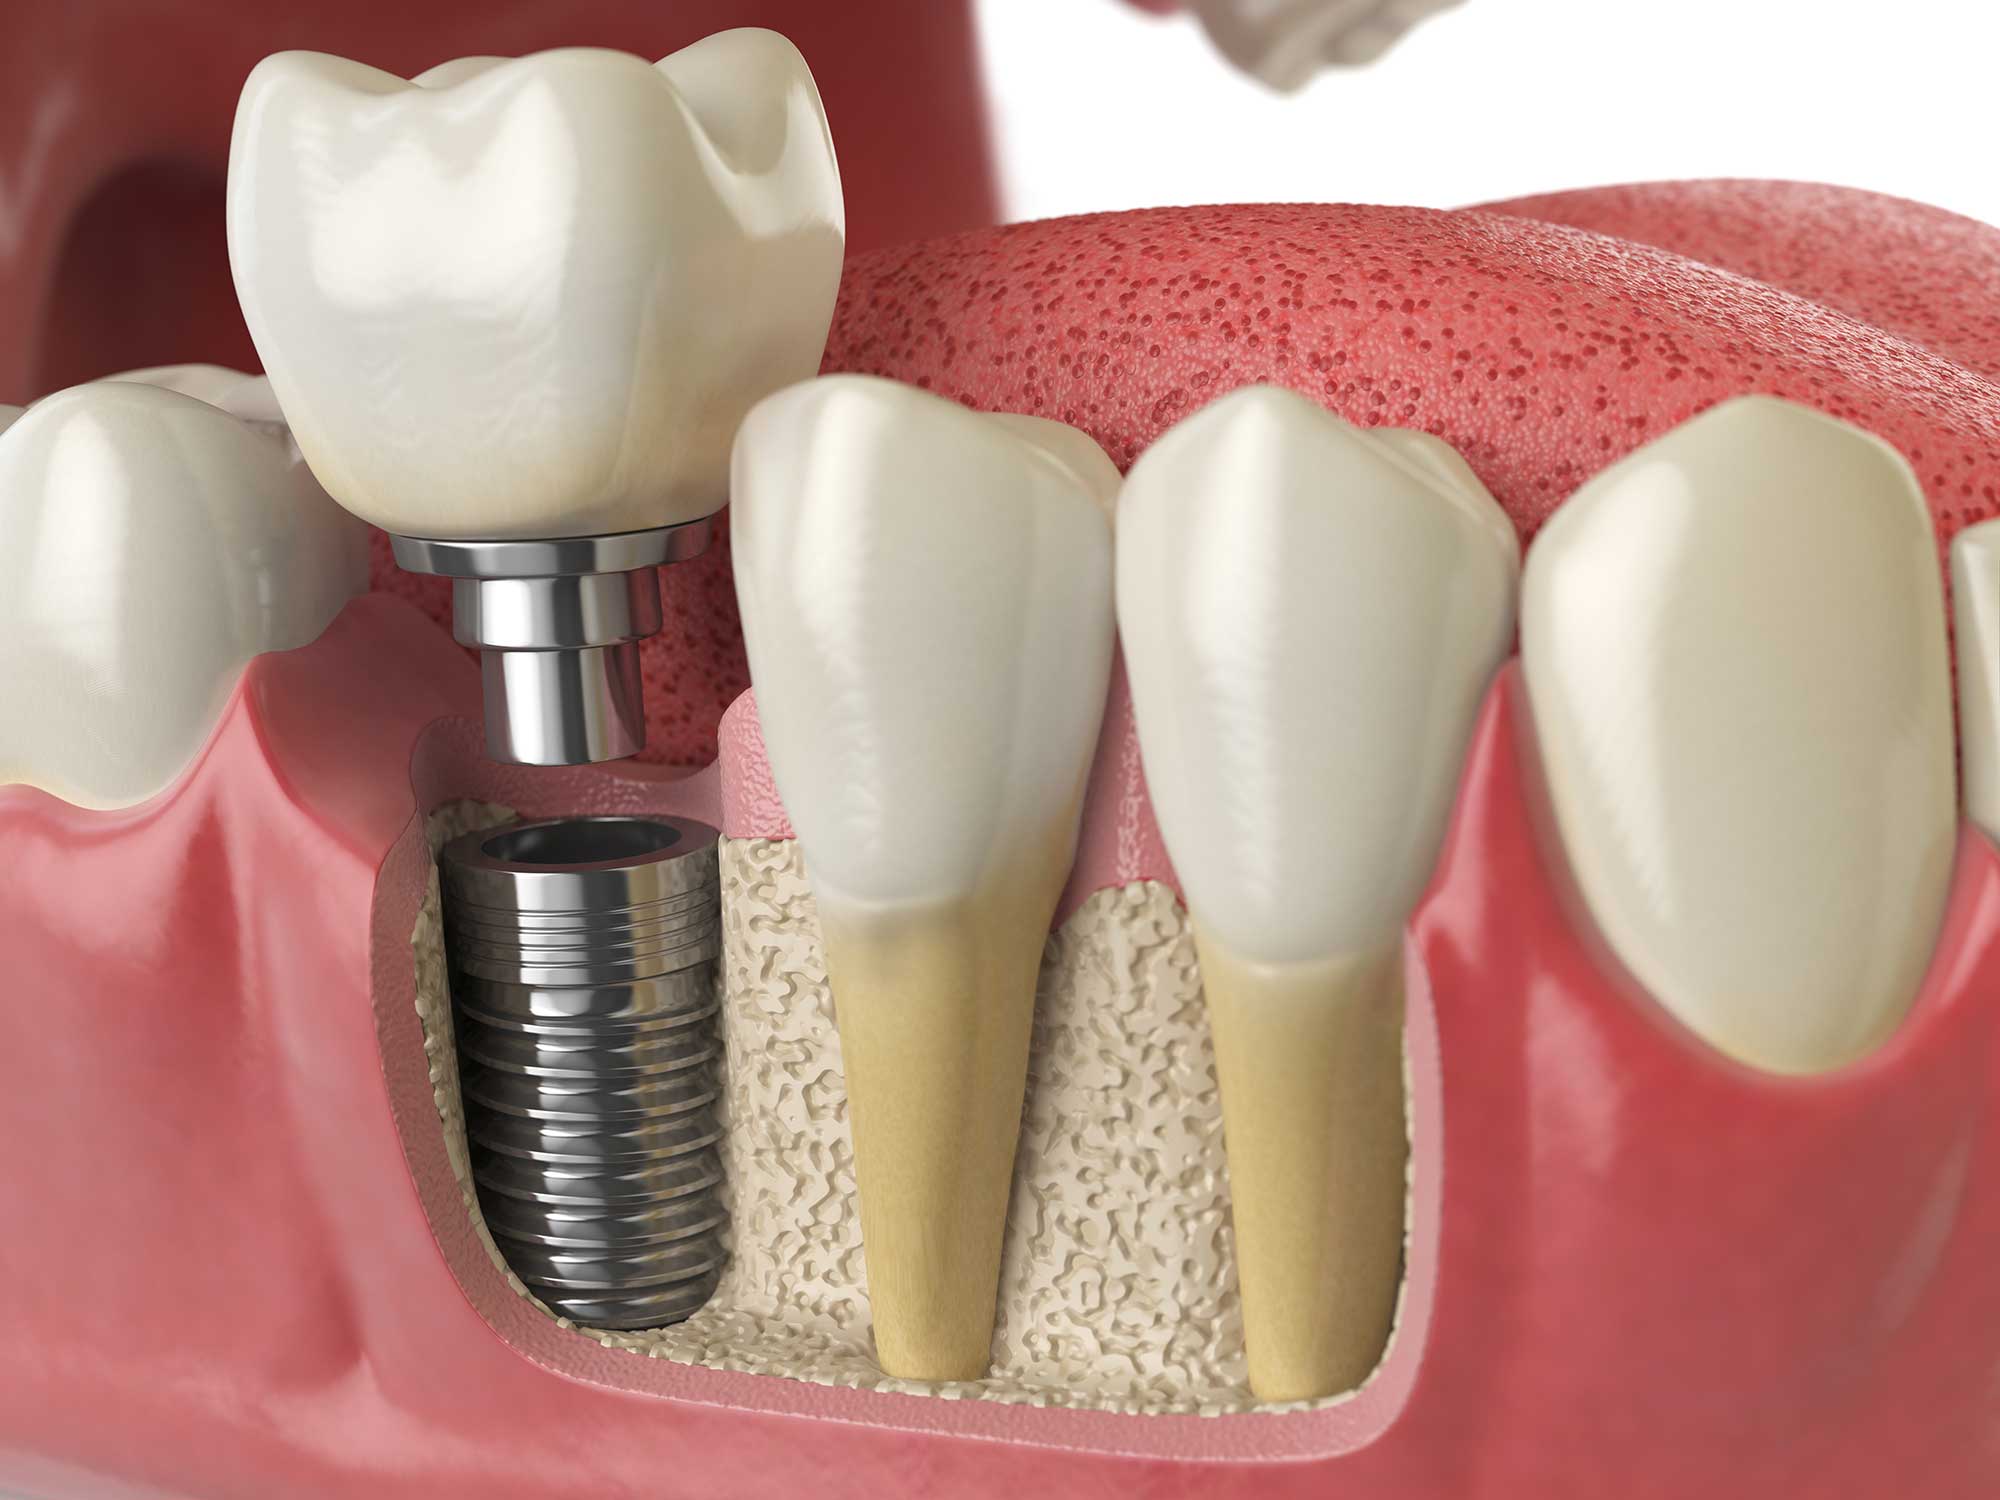

Dentures, bridges, and implants can all replace missing teeth. However, dental implants often prove the best, longest-lasting solution for restoring one or more lost teeth. They involve three main parts:

Once a patient is determined to have enough bone, then the procedure can move along. Placing the titanium post is typically quick and straightforward. Your surgeon places the post through a small opening in your gums at the precise location you need. Some patients may need a bone grafting treatment prior to the implant placement or at the time of implant placement to restore lost bone mass. We then clean the area and close any incisions. In most cases, initial recovery takes less than 2 weeks, but you can go about your daily routine the day after the implant placement.

Over the next 3-6 months, the implant will permanently fuse to the jawbone through osseointegration. During this time, we see patients for follow-up visits to ensure everything is progressing well. We will create impressions of your bite and implant, which are used in the lab to create an abutment and a custom crown that fits naturally in your smile.

When the lab finishes your prosthetic, they send it to us and we can place it on your implant at your next visit. We check that everything fits, looks comfortable, and feels natural. We then permanently secure it to the abutment, and you can start to enjoy your new tooth.

Single-tooth implants are the most commonly used dental implants for tooth replacement and replace one tooth at a time. They involve a titanium post, an abutment, and a single dental crown on the top. Patients can have one or more of these types of implants, depending on their situation.

First, we choose from a range of post sizes to select one suitable for your smile and jaw structures. Once it is placed and integrated to your bone, we take impressions that are sent to the lab, where they are used to create an abutment and crown to match your smile's features. Our lab partners use medical-grade porcelain and composite materials to craft a natural-looking crown from scratch.